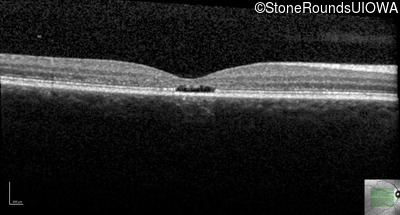

Age at visit: 17 years

OD OS

This 17 year old female first noted problems with her visual acuity around age 13 when she had trouble seeing the projector from the back of the classroom.

Age at visit: 16 years

Age at visit: 18 years

Age at visit: 22 years